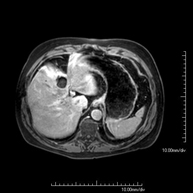

- RM d'Abdomen

Prova diagnòstica no invasiva que consisteix en l'obtenció d'imatges d'alta definició anatòmica de l'abdomen mitjançant l'ús d'un camp electromagnètic i ones de ràdio (amb un emissor i un receptor). No utilitza radiació ionitzant. En aquesta exploració s'inclouen el fetge, el pàncrees, la melsa, la via biliar, la vesícula biliar, les glàndules suprarenals, els ronyons, l'aorta abdominal, la vena cava inferior, l'estómac, el duodè, etc. En alguns casos caldrà emprar contrast paramagnètic (Gadolini) per caracteritzar les lesions. - RM Pelvis femenina

Prova diagnòstica no invasiva que consisteix en l'obtenció d'imatges d'alta definició anatòmica del fetge mitjançant l'ús d'un camp electromagnètic i ones de ràdio (amb un emissor i un receptor). No utilitza radiació ionitzant. Es realitza per estudiar qualsevol lesió localitzada en el fetge. Normalment es requereix l'ús de contrast paramagnètic (Gadolini) per caracteritzar les lesions. És necessari realitzat la prova en dejú (6 hores). - RM de Ronyons